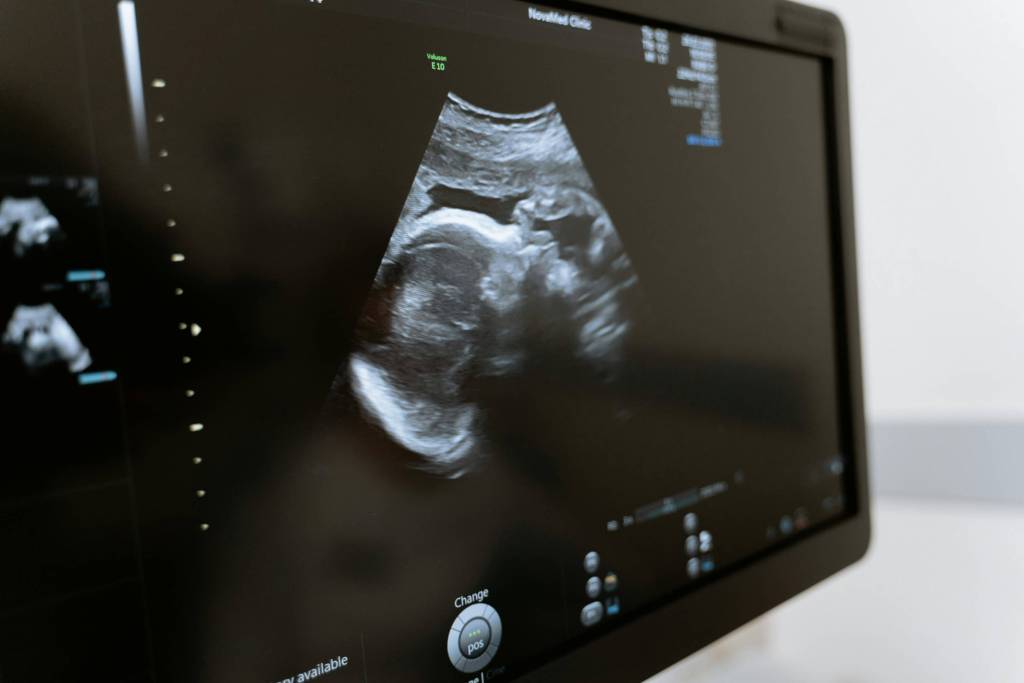

Producido tanto por la futura mamá como por su bebé, y posteriormente reabsorbido por él, el líquido amniótico se convierte en el reflejo de los buenos intercambios entre la madre y su bebé y, también, del buen desarrollo de este último. De ahí que, con cada visita, el médico esté muy atento al volumen existente de líquido amniótico a través de las ecografías.

¿Cómo se diagnostica?

Un aumento de peso repentino, o la aparición de edemas suelen ser también señales de advertencia.

En cualquier caso, la ecografía será finalmente útil para confirmar el diagnóstico. Para ello, el especialista mide las áreas negras que encontramos en la pantalla, y que se encuentran ubicadas alrededor del bebé: son las que se corresponden con el líquido amniótico. Así, con estas diferentes medidas, puede establecer el índice amniótico. A partir de ahí puede hacer el diagnóstico: hidramnios moderado o hidramnios severo.